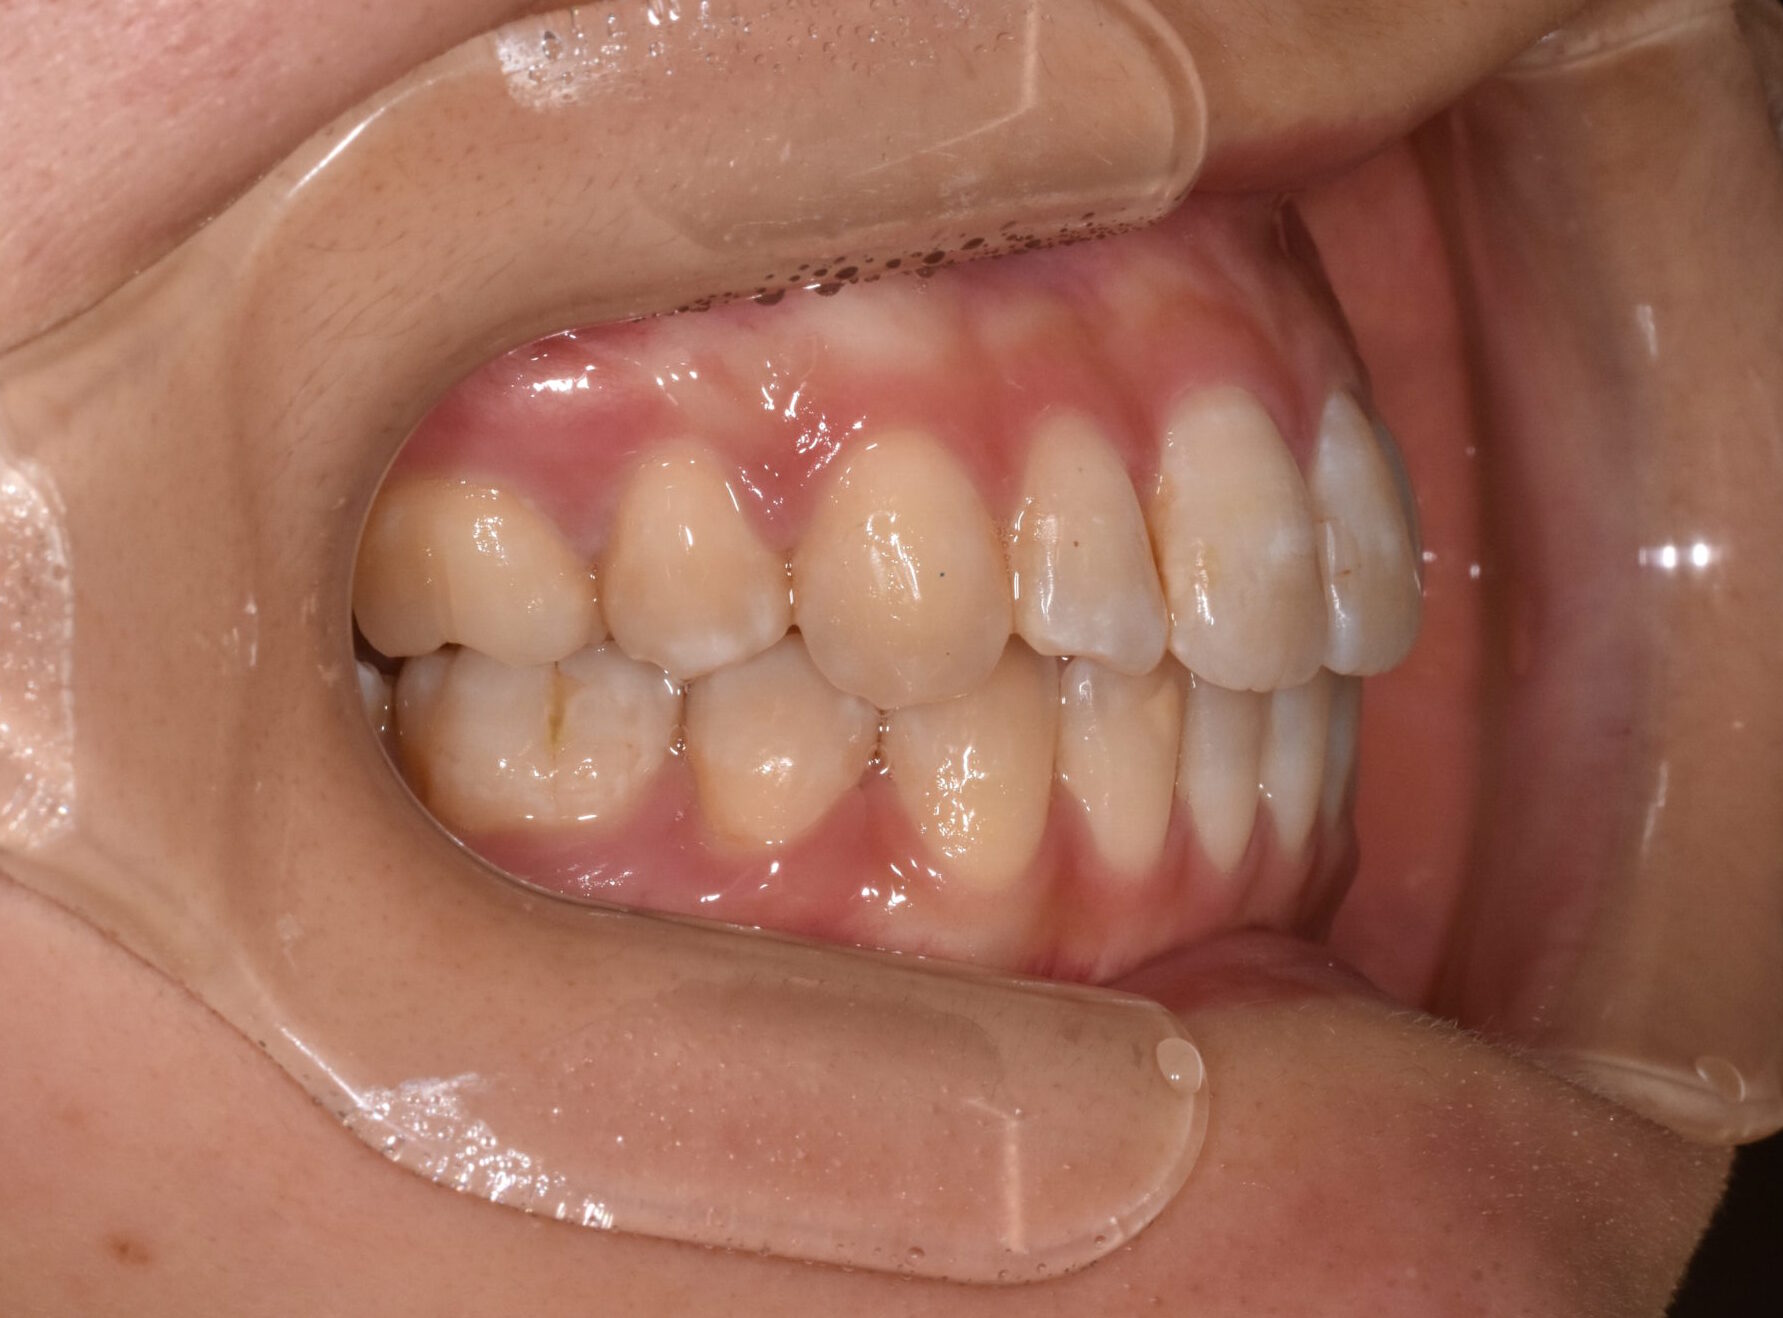

治療後

・抜歯によりスペースを確保し、前歯の位置と角度をコントロール

・奥歯の高さを調整し、前歯がしっかり噛むように改善